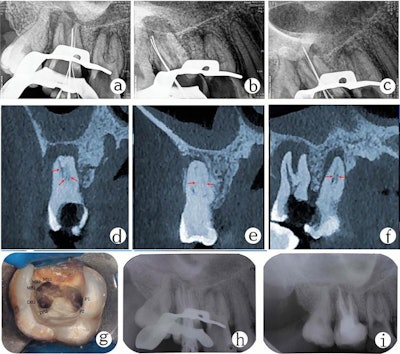

On radiographs, clinicians could see the pulp chamber was extended, the pulp floors showed apical displacement, the roots were short, and both teeth showed periapical translucency. The teeth were diagnosed as showing symptomatic apical periodontitis and mesotaurodonts. Mesotaurodontism is a classification of taurodontism in which the teeth are notably larger in size and have shortened roots and an enlarged pulp chamber.

Root canal therapy was recommended. Using a dental operating microscope, the dentist removed residual decay and prepared the access opening. Three orifice openings were identified in the pulp chamber. A closer look revealed complex patterns in both molars. An extra root canal orifice was concealed approximately 2 mm to 3 mm under the prepared canal orifice of the mesiobuccal and palatal canals in tooth #17.

CBCT scans gave a better view of the teeth and verified the findings. Clinicians prepared six canals in tooth #16 with two in the mesiobuccal root, two in the distobuccal root, and two in the palatal root. They also prepared seven canals in tooth #17: three in the mesiobuccal root, two in the distobuccal root, and two in the palatal root, the authors noted.

During root canal preparation, they could see that two of the canals in the mesiobuccal root of tooth #17 were joined together. The canals in the palatal roots were separated in the middle of the palatal root and met together in the third apical. X-rays and an electronic apex locator were used to determine the roots' working lengths. The preparation was completed, and the access cavity was sealed with temporary filling.